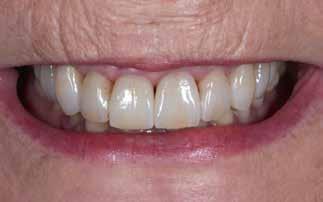

Interdiszciplináris fogászati kezelés myofunkcionális készülék, alignerek és protetikai ellátás alkalmazásával

MED. DENT Abradált frontfogakkal rendelkező felnőtt páciens interdiszciplináris kezelése